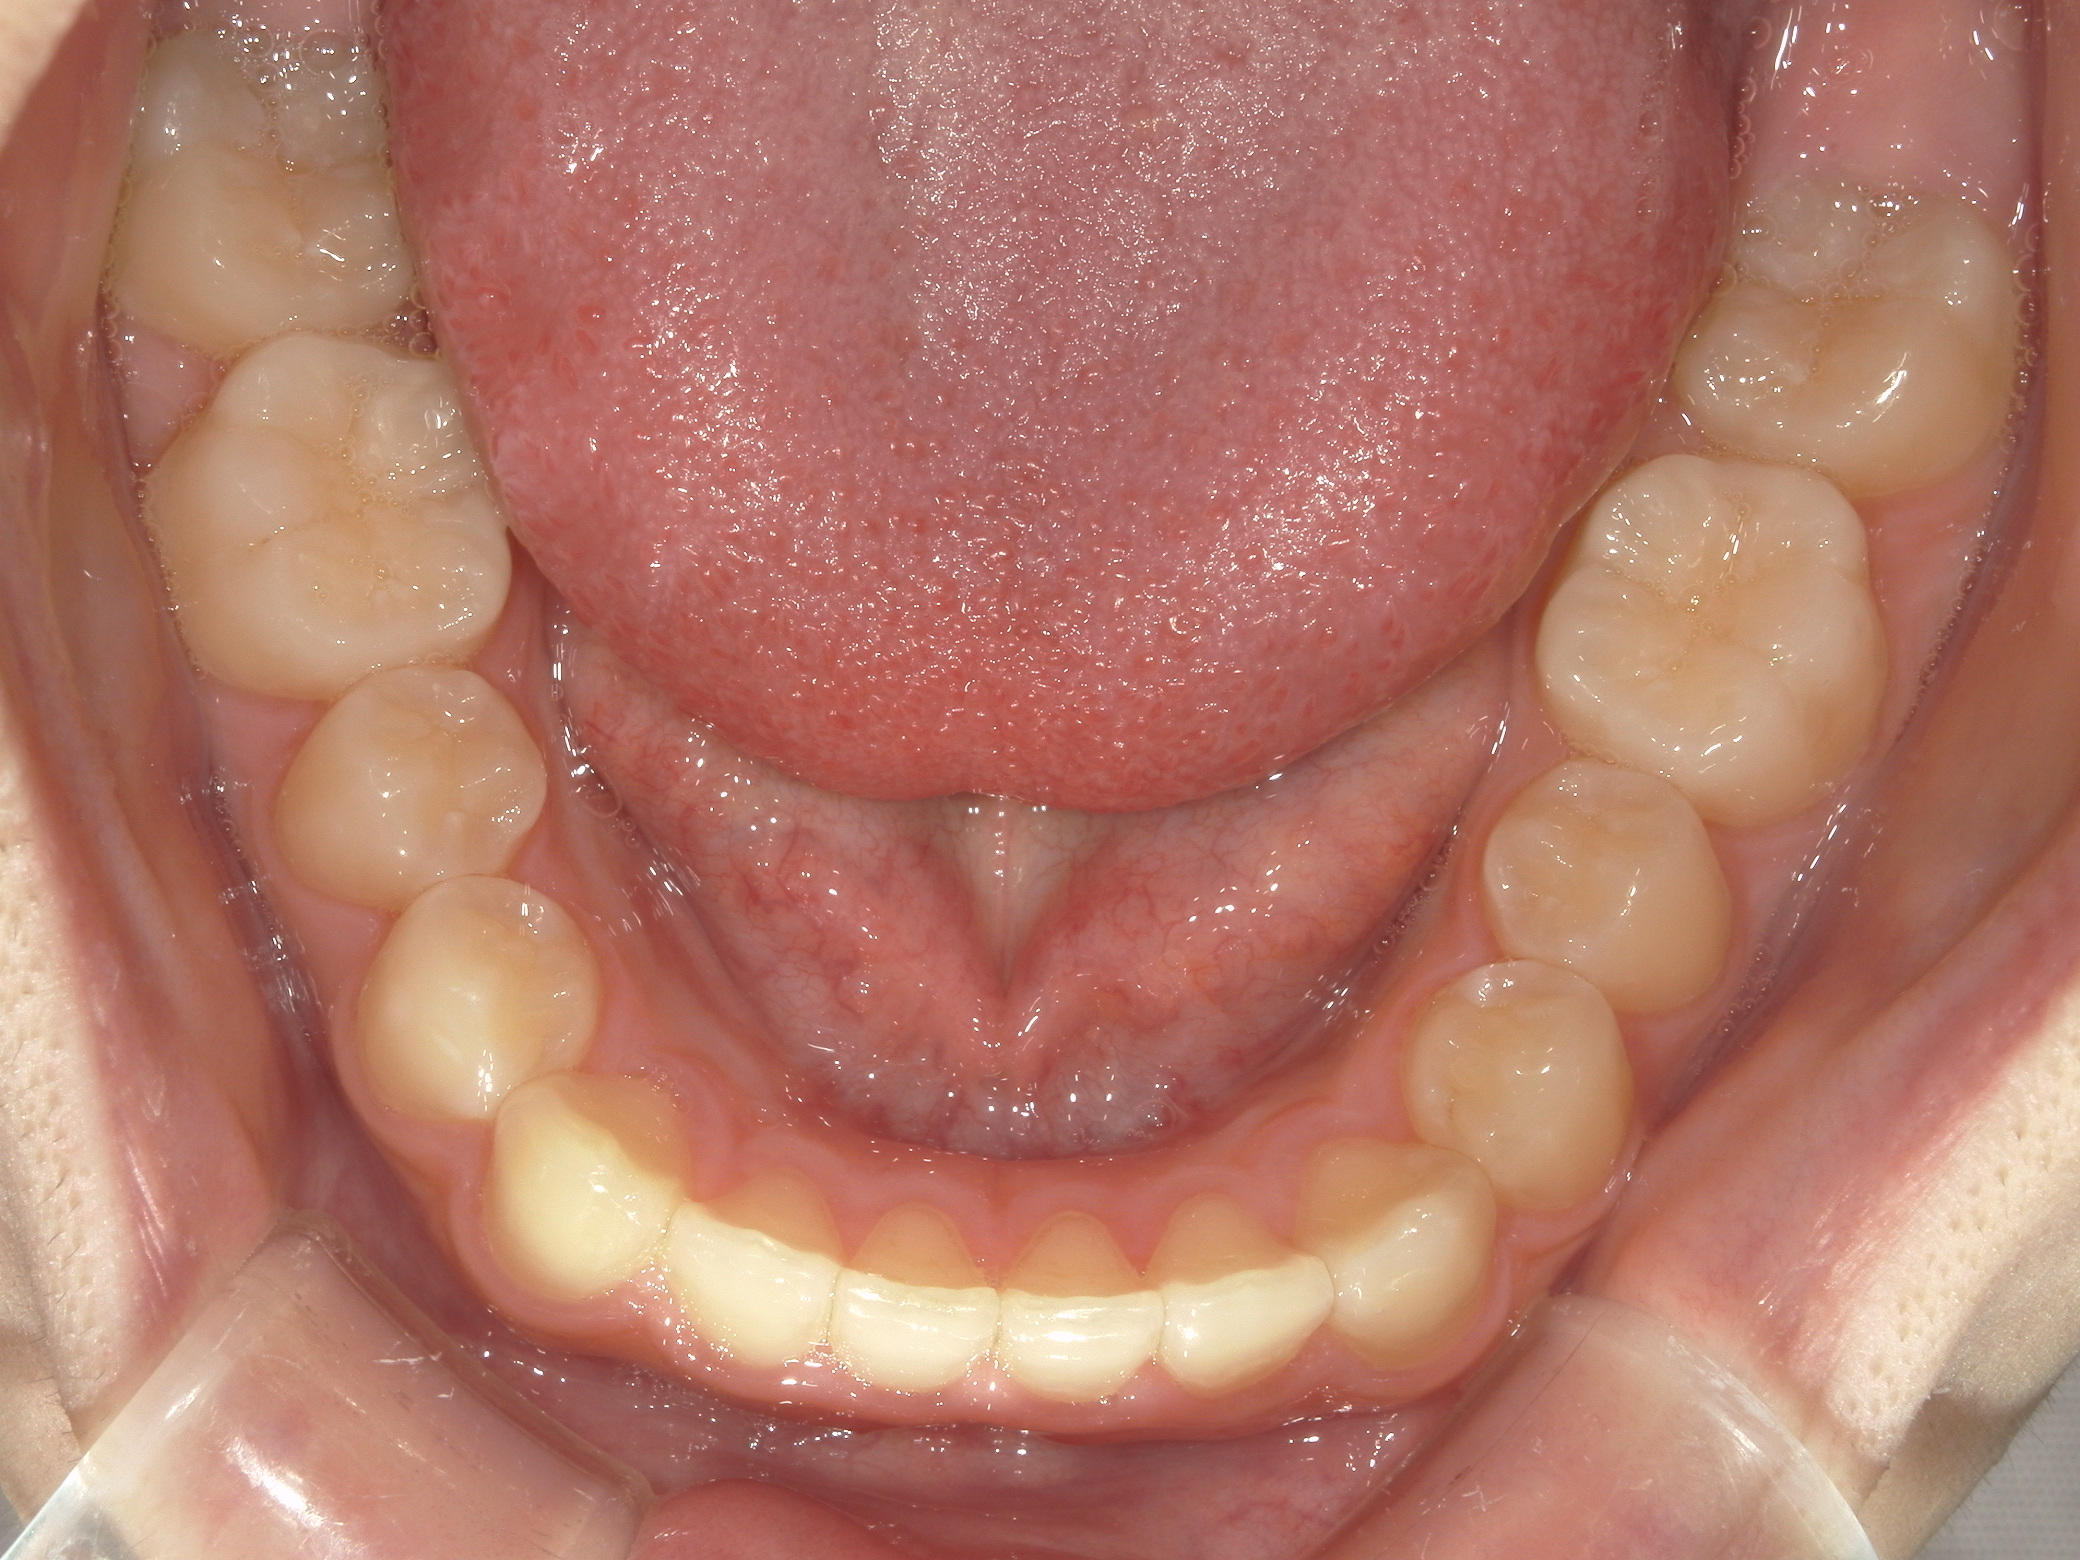

インビザライン矯正 症例(19)

主訴: 左上犬歯が出ているのが気になる